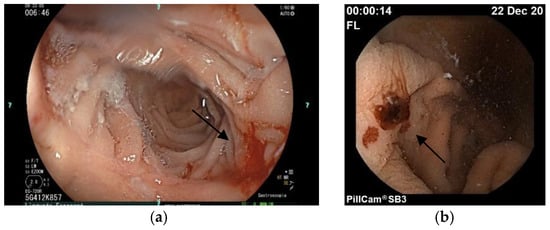

3.3. Case Report